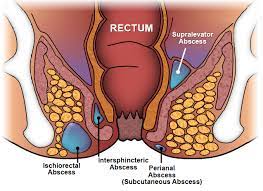

Overview

Value added benefits of the Fistulectomy - Low:

Overview

Value added benefits of the Fistulectomy - Low - With Laser:

Overview

Value added benefits of the Anal Fitsula:

Overview

Value added benefits of the Fistulectomy - High - With Laser:

Overview

Value added benefits of the Haemorrhoidectomy - Routine:

Overview

Value added benefits of the Stapler Haemorrhoidectomy: